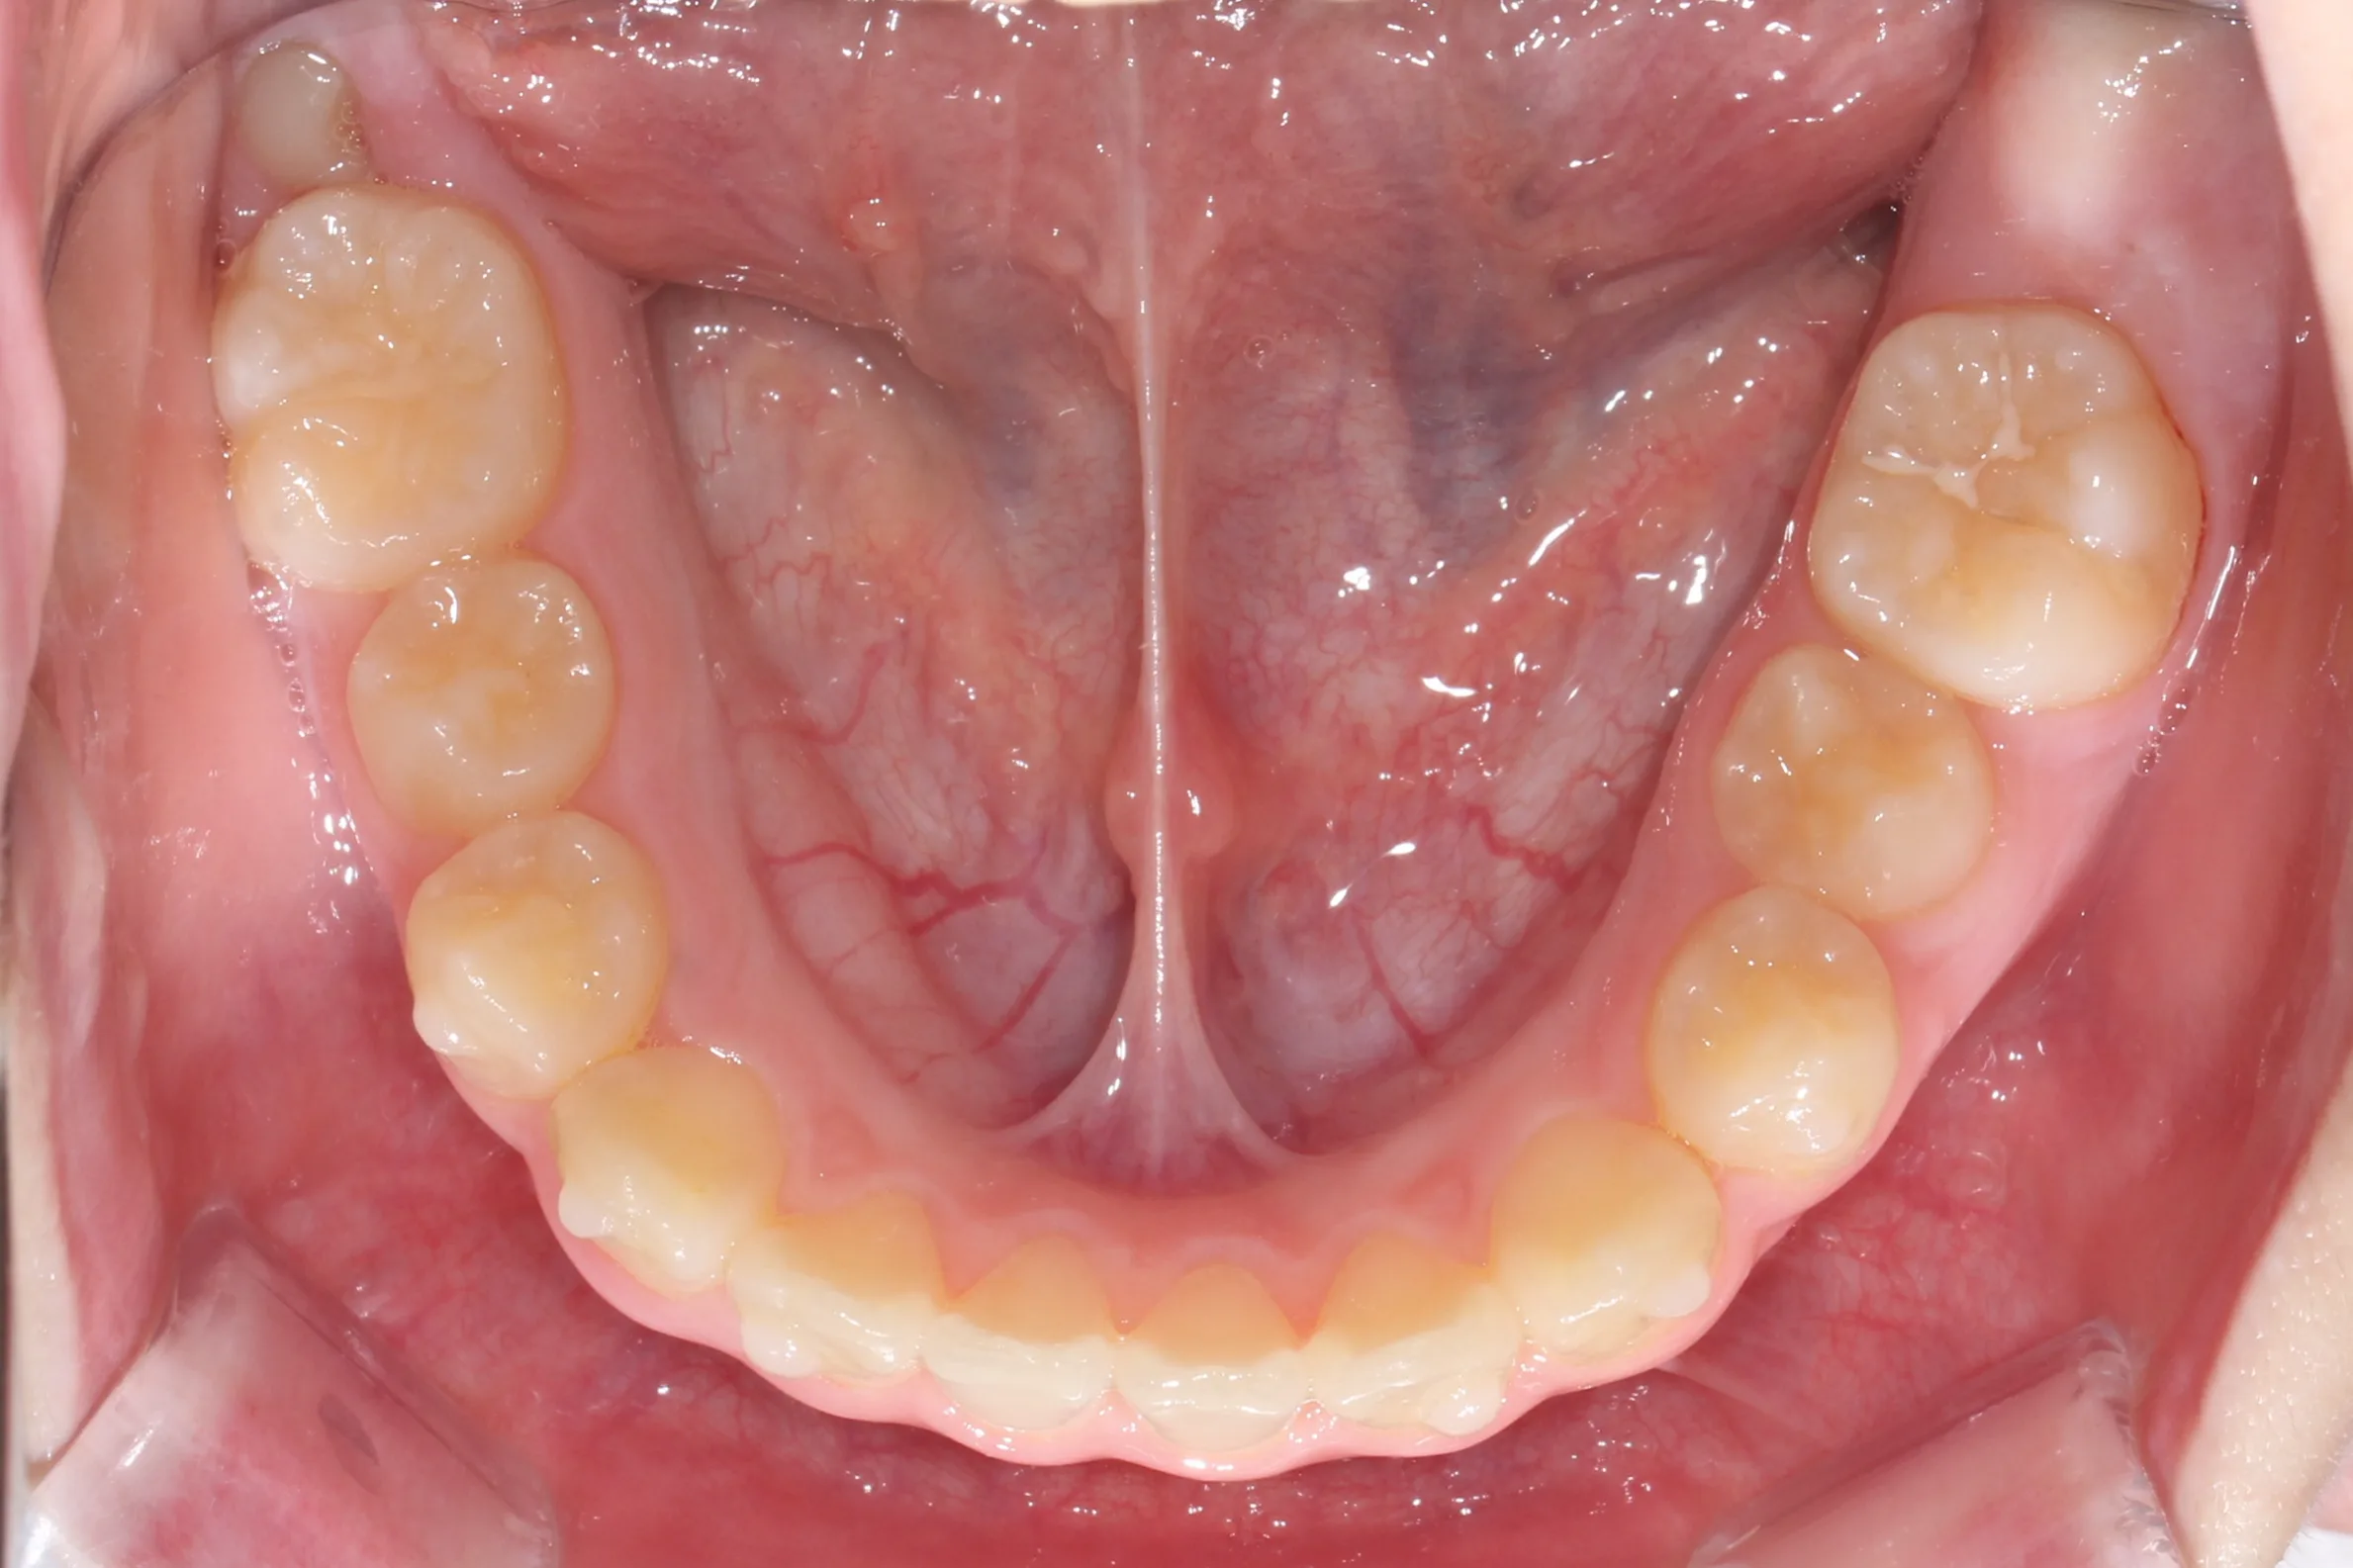

만 11세 환자분께서 튀어나온 앞니와 다물어지지 않는 입술 때문에 내원하셨습니다. 검진 결과 상악 전돌을 동반한 2급 부정교합(Class II malocclusion) 상태였으며, 아래턱의 성장이 다소 부족하여 골격적인 조화가 필요한 상황이었습니다.

이번 치료에는 인비절라인 퍼스트(Invisalign First)에 하악 전방 견인(Mandibular Advancement, MA wing)을 추가하여 치료를 진행하였습니다. 성장기라는 시기적 특성을 적극 활용하여 아래턱의 점진적인 성장을 유도하고, 과도한 상악 전치부 돌출을 개선하는 데 치료의 핵심 전략을 두었습니다.